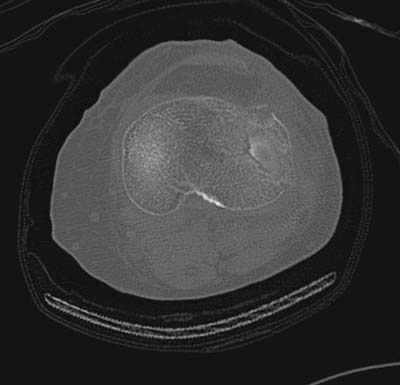

Устранение импрессии, костная аутопластика, остеосинтез опорной пластиной

оперировать вероятнее всего надо, импрессия приличная , думаю около 1,5 см, только вот она в задних отделах, преимущественно. Если ставить опорную пластину, то делать это нужно сзади, иначе никакой опорности, а задний котртекс по КТ похоже замят

задний кортекс не повреждён. Подойдёт рафтинговая пластина.

Учитывая, что у пациента молодой возраст(судя по рентгенограммам,абсолютно показано восстановление суставной линии: подменисковый доступ,подъём импренированной части мыщелка, костная аутопластика, остеосинтез, решение вопроса с мениском (шов либо парциальная резекция)).

Как подсказывают, можно с противоположной стороны приподнять сустав и заполнить костный дефект. Параллельные винты создадут достаточную опору, но иногда buttress plate за счет диафиза создает дополнительную стабильность. Структуральный материал для профилактики от раннего коллапса, и пластическим материалом служит более твердый синтетический материал (Osteoset DBM) или аутокость.

Для лечения некоторых видов центральной импрессии (Schatzker III) можно применить методику Balloon tibioplasty, которая позволяет приподнять сустав без дополнительных доступов. Для информации здесь недавний пример, дефект заполнен жидкой формой композитного материала PRO-DENSE: http://www.wmt.com/prodense/product_overview.asp